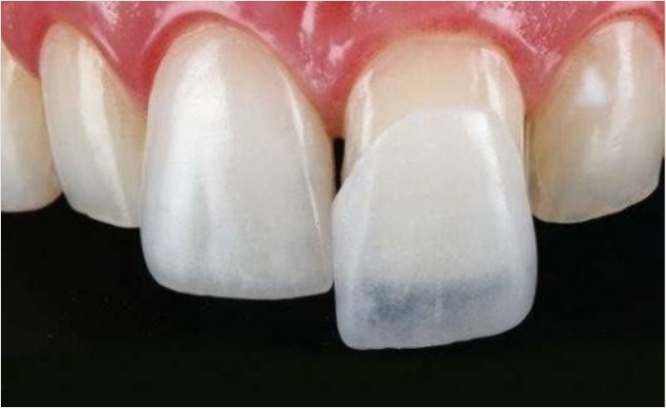

아무리 완벽한 치료와 좋은 재료여도 가장 좋은 것은 자연치아입니다.

개인의 구강상태를 고려하여 가장 적합한 보철물을 통해

치아의 기능적 회복 및 심미적인 부분까지 개선하는 치료입니다.

치아의 겉 표면을 최소삭제 후 얇고 자연스러운 인공치아를

치아 겉면에 덧붙여 이상적인 형태로 복원시키는 치아성형술입니다.

불만족스러운 치아의 배열, 색상, 크기 등을 수정하여

자신감있는 미소로 밝은 인상을 만듭니다.